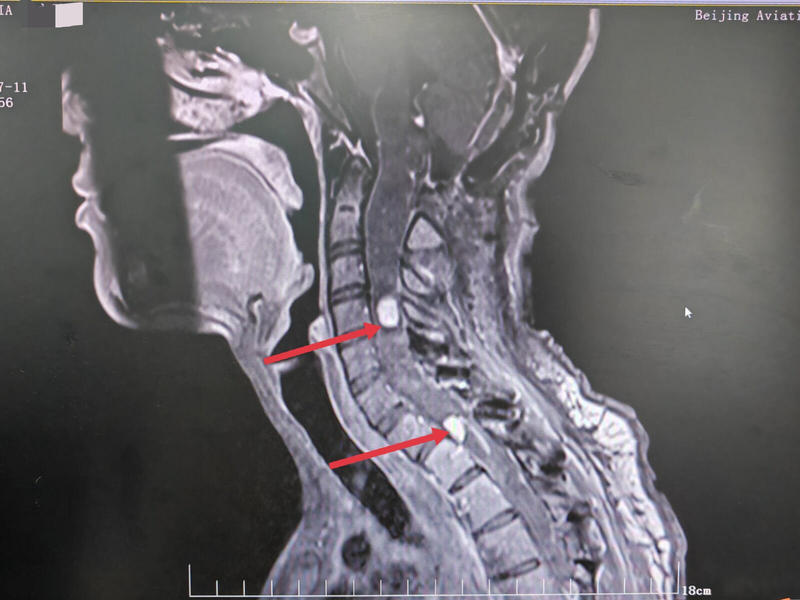

患者女性26岁,于2023年6月开始出现双上肢麻木,麻木症状呈进行性加重。7月4日于青海省人民医院行颈椎核磁提示:延髓—胸2椎体后方脊髓肿胀伴多发异常信号。患者及家属为进一步治疗来我科。根据影像可见颈胸椎管内占位诊断明确,考虑血管母细胞瘤,目前症状明显,建议手术切除病变。完善术前检查后行椎管内占位性病变切除术,术中切开颈4水平硬膜,纵行切开脊髓可见病变与脊髓边界不清,显微镜下沿脊髓与病变边界分离并全切病变组织。后于颈7-胸1水平切开硬膜,纵行切开脊髓可见病变位于腹侧且与脊髓粘连明显,病变牵拉分离易导致脊髓损伤,双极灼烧病变。影像学可见颈1—3水平脊髓增粗明显,咬骨钳咬除颈2.3椎板及棘突予以减压。手术顺利,术后恢复良好。